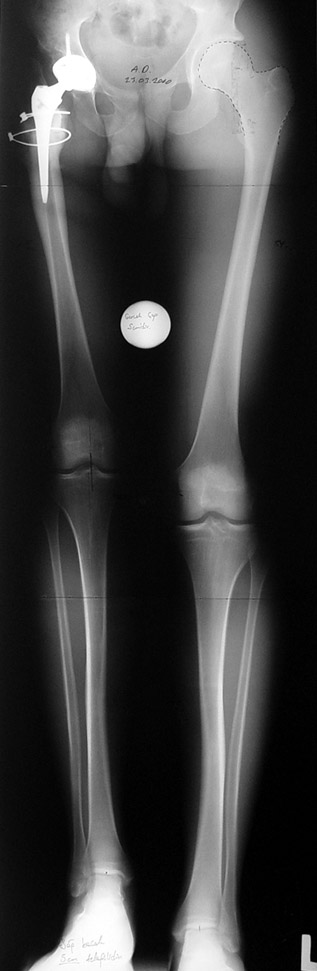

Vaka 1